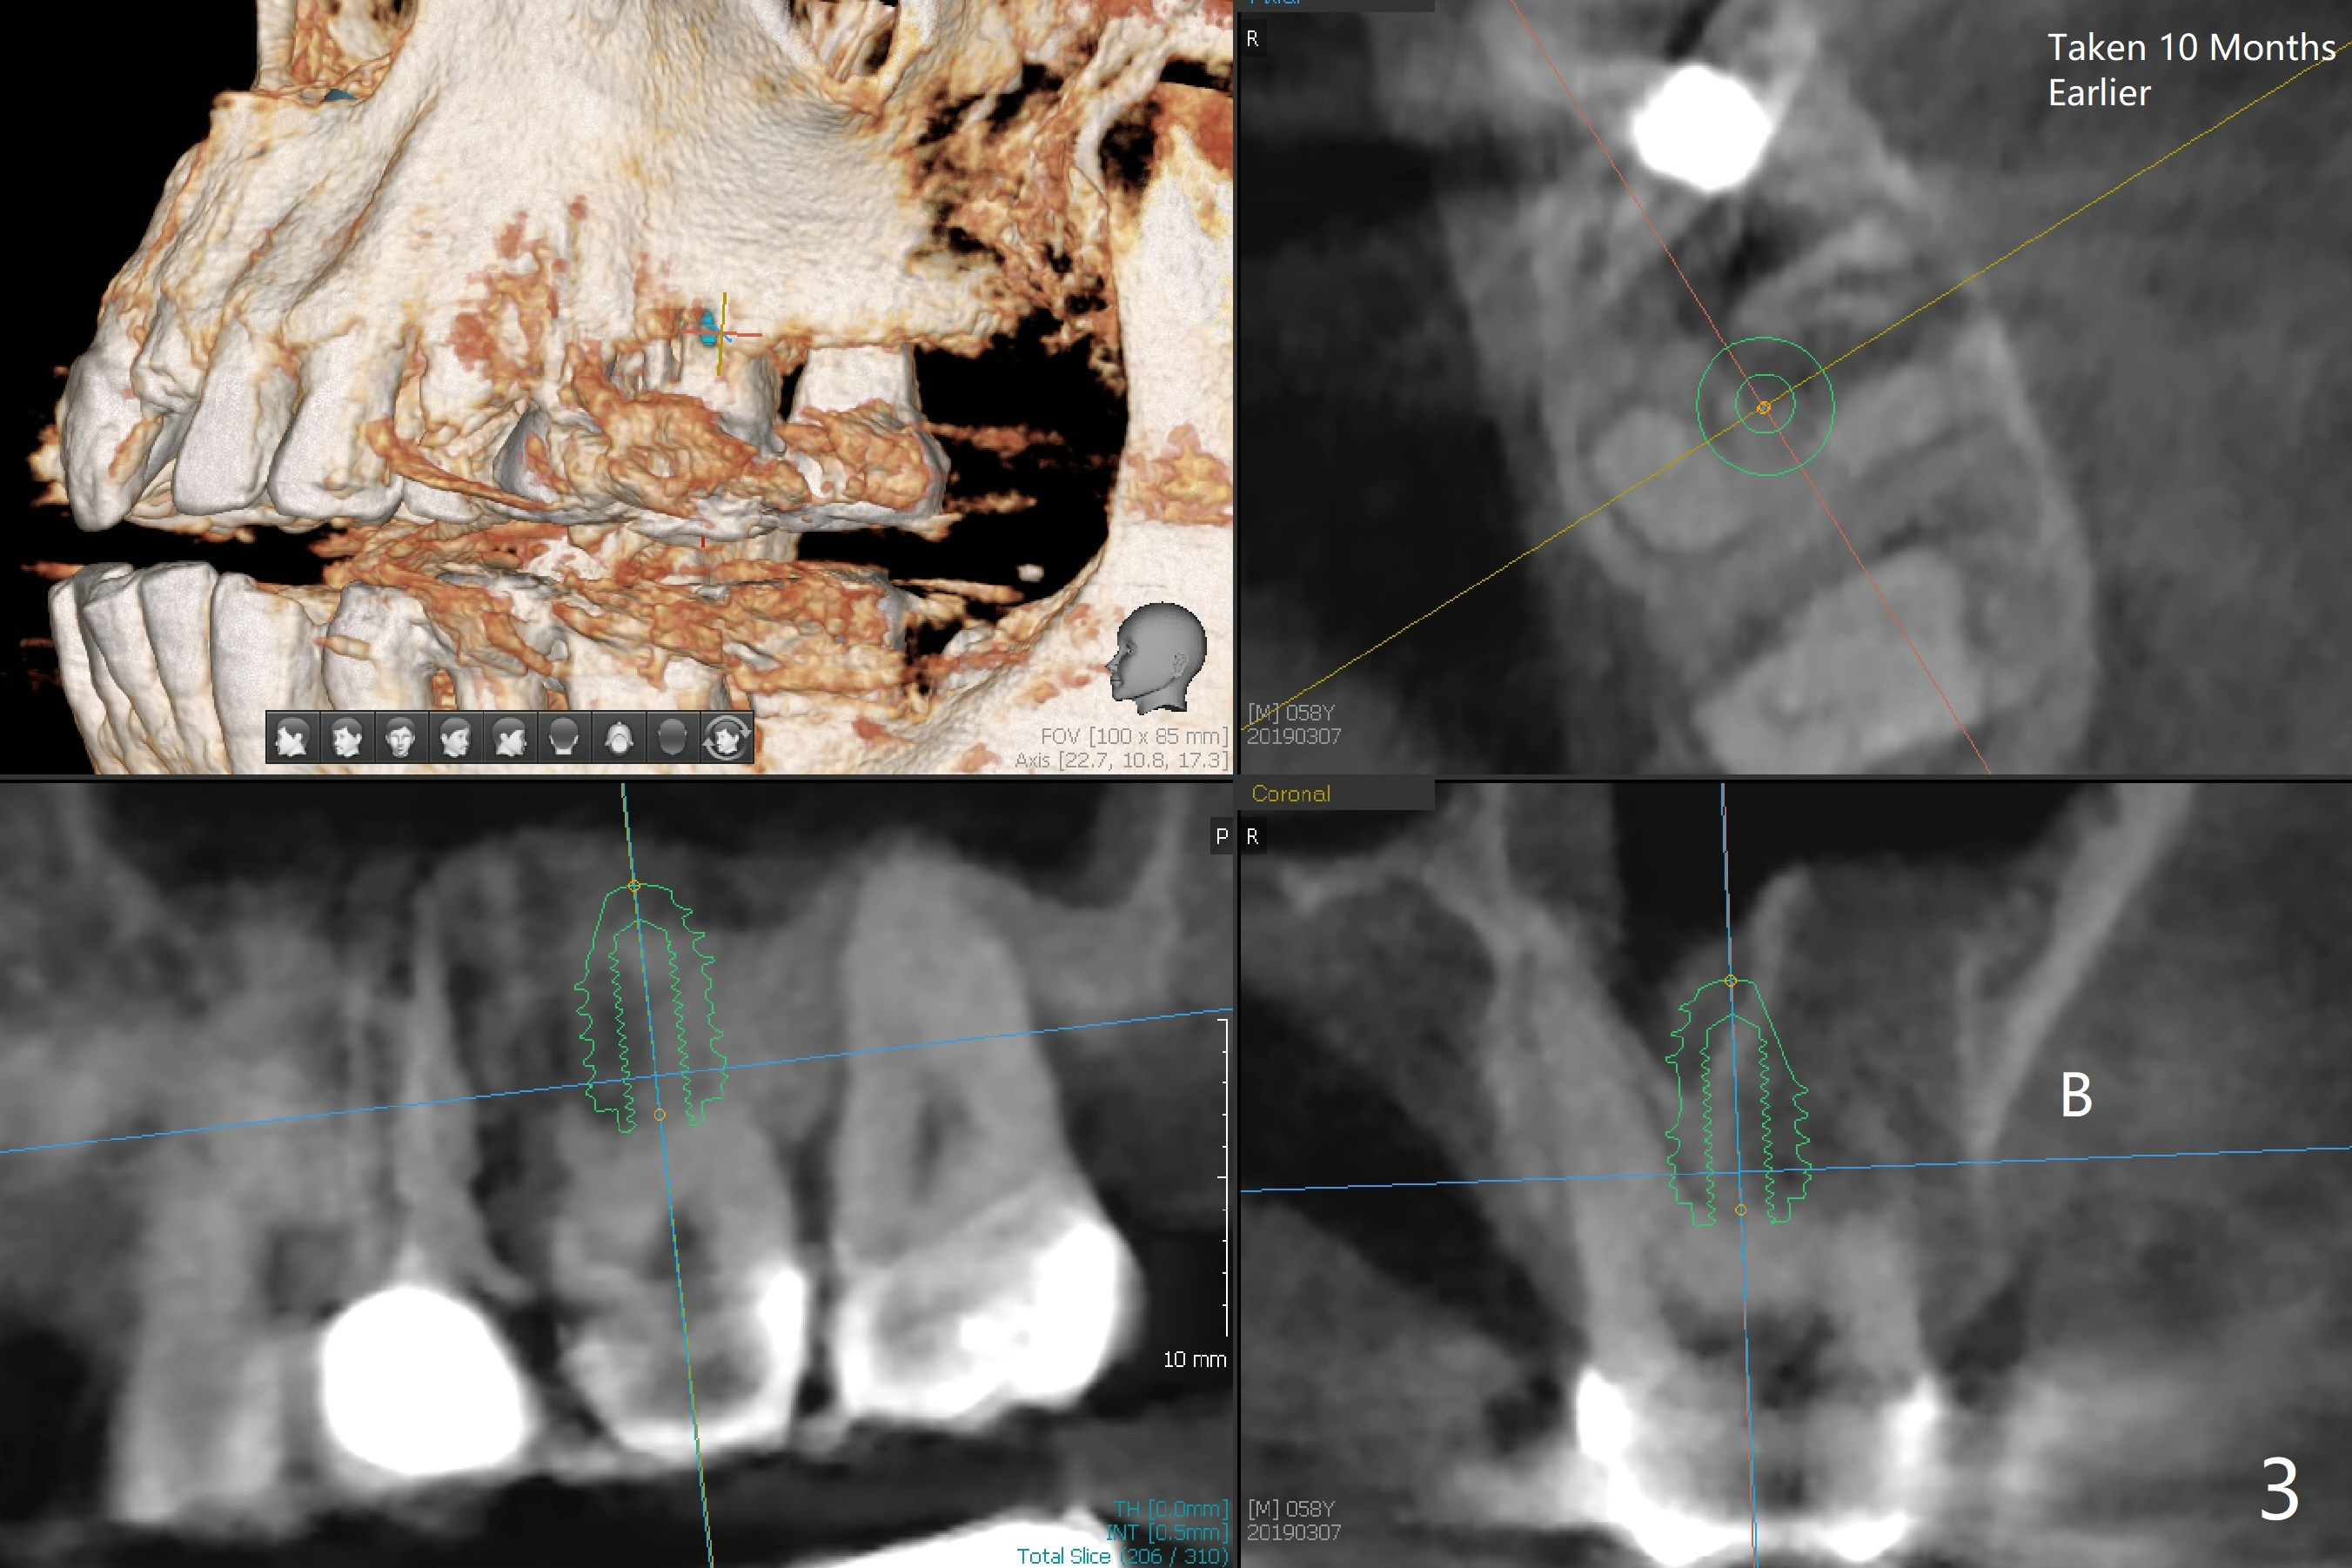

The vertical mesiobuccal root fracture of #14 of a 59-year-old man has become worse in the last 10 months. The mesial portion appears to be separate and have migrated mesiobuccal from its original place (Fig.1,2). CT taken 10 months earlier shows that the septal bone seems to be thin (Fig.3). Use IS drills (pointed to 3 mm in diameter) with 2 or 3 mm stoppers to start osteotomy and Magic Sinus Lifter. Place a 4.5x9 mm FC. If the latter fails, use sticky bone for sinus lift and socket preservation, followed PRF membranes (3-4), Cytoplast (small piece, smaller than the wound) and setting acrylic to close the sockets, including buccal defect. Take new CT (5x5) for update.